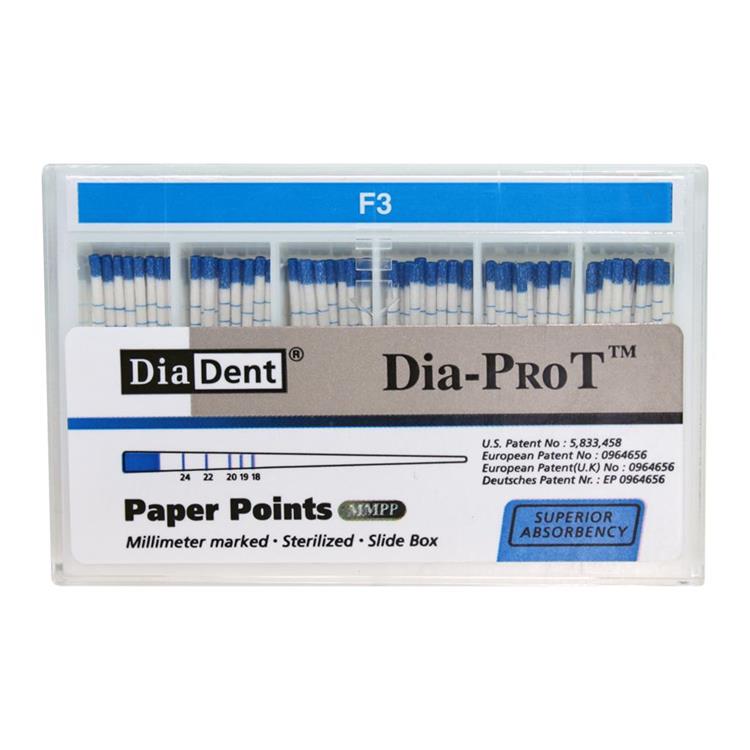

Endodontics: Gutta Percha & Paper Points.